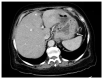

Primary gastric cancer remains one of the most prevalent malignancies worldwide. Often patients remain asymptomatic until it is detected at an advanced stage with a poor prognosis. Thus, it's characteristically difficult to initially diagnose until it becomes late stage, at which point prognosis becomes poor. Pernicious anemia is a classic risk factor for the development of primary gastric cancer, but is uncommonly seen in clinical practice. Over time, patients who produce the autoantibodies to intrinsic factor that cause pernicious anemia typically will present initially with clinically significant megaloblastic anemia and peripheral neuropathy. However, patients can also present with more nonspecific signs and symptoms. Thus, clinicians should remain vigilant as circulating anti-intrinsic factor antibodies only worsen the disease over time and increase the risk of developing primary gastric cancer. This report not only presents the rare concurrent diagnosis of pernicious anemia and gastric cancer, but also aims to increase clinical awareness of these two conditions' classic association because early diagnosis and treatment significantly impacts morbidity and mortality.